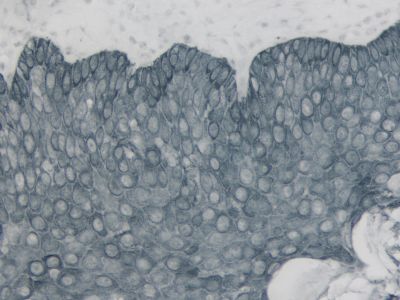

- Enhanced accessibility to nuclear and membrane antigens

The peroxidase micropolymers of the ImmPRESS HRP polymer reagent limit steric interference and provide enhanced accessibility to the target, avoiding the disadvantages of other polymer systems that use large dextrans or other macromolecules as backbones. The result is crisp, strong staining of antibody targets, especially nuclear and membrane antigens (such as Ki67, estrogen receptor, bcl-2, CD3, CD8 and CD10) and greater sensitivity than other polymer systems.

The staining procedure is simple as shown in the diagram below. Following a blocking step with the diluted normal horse serum, sections are incubated with primary antibody. After a brief wash, the appropriate ImmPRESS Reagent is added to the sections and incubated for 30 minutes. Sections are again rinsed and the slides are developed with the peroxidase substrate of choice.